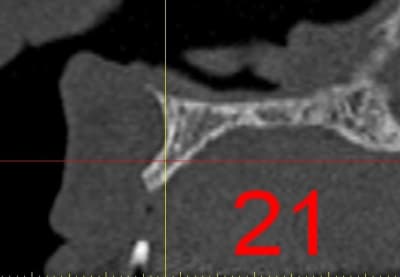

La première diapo est un essai pour justifier le concept (os non destiné à une utilisation greffe)

la deuxième est "tapée" dans une tête de femur de mauvais qualité (rejetée)

la troisième et suivante ce sont "les greffons" définitifs.

La précision 3D du scan est elle suffisante pour une adaptation passive sur l'os réel ?

La tu nous montres sur un stereolitique obtenu à partir du scan, ok ça colle mais en bouche ?